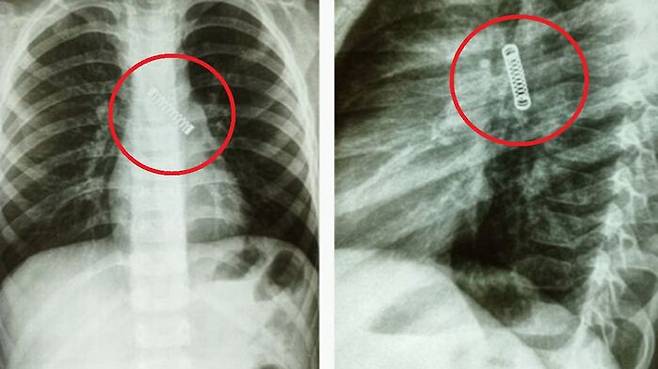

3달째 기침이 멈추지 않아 병원을 찾은 5살 아이의 폐에서 3cm 길이의 금속 스프링이 발견됐습니다.

최근 영국 매체 더 선, 더 미러 등에 따르면 파라과이 국립호흡기병원 의료진은 지난 8일 A 군(5세)의 폐에서 3cm 길이의 금속 스프링을 제거하는 수술을 진행했습니다.

의료진은 문제의 스프링이 A 군의 폐에 약 3개월간 박혀있었던 것으로 보고 긴급 치료를 위해 국립호흡기병원으로 이송, 스프링 제거 수술을 성공적으로 마쳤습니다.

의료진이 X-레이를 촬영한 결과, 뜻밖에도 왼쪽 폐에 금속 스프링이 박혀 있었습니다.